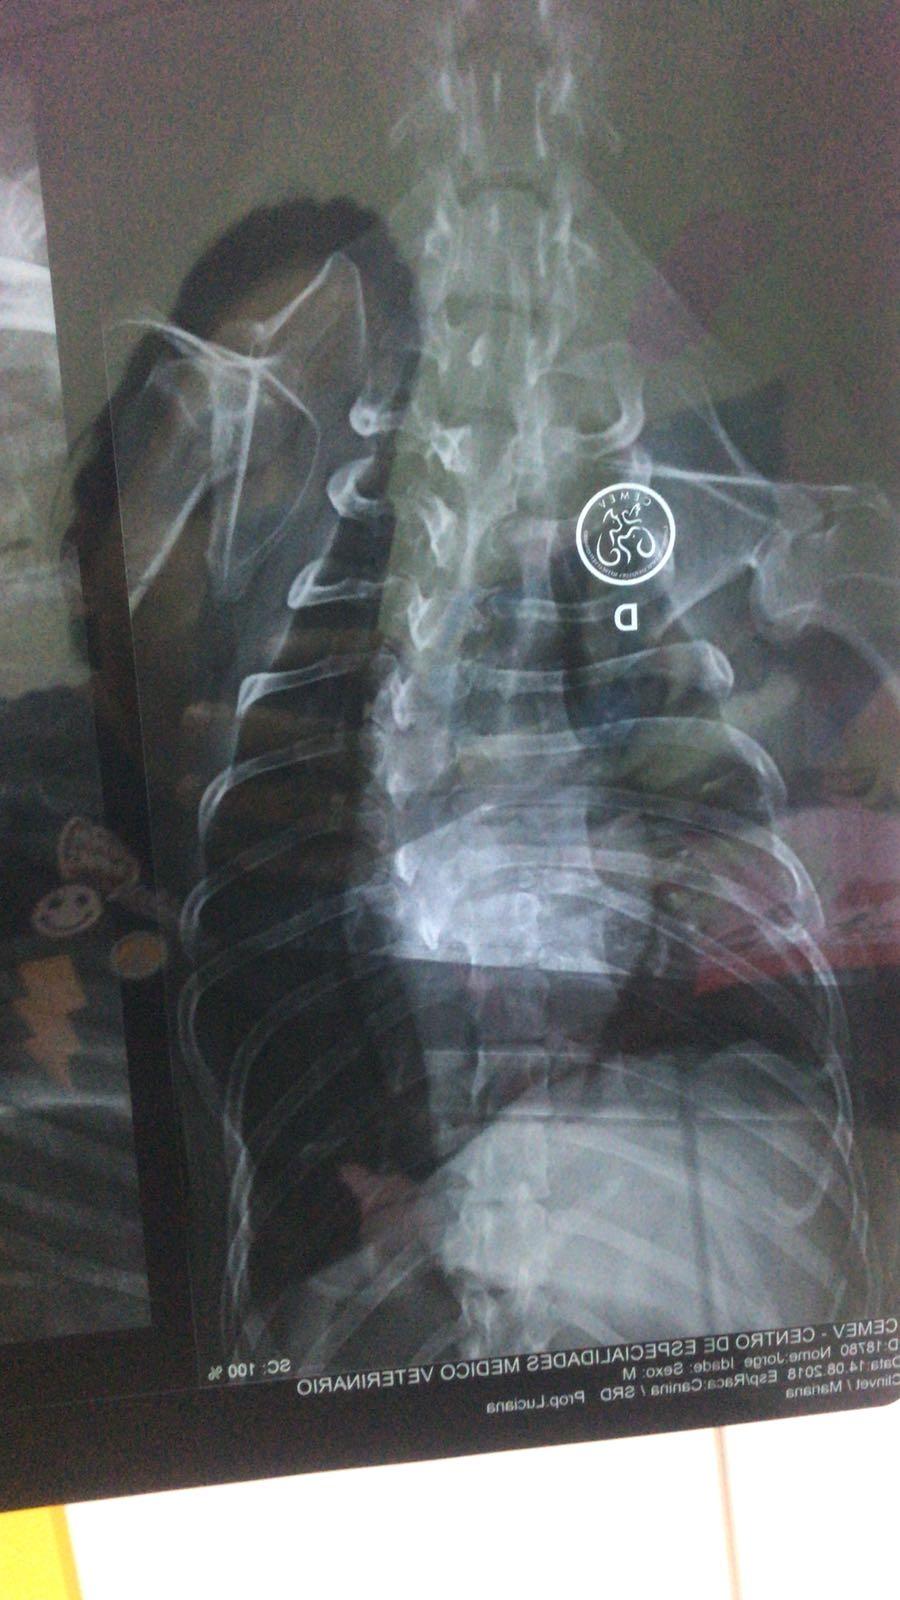

O diagnóstico, obtido a partir de uma radiografia na última terça-feira (14), foi a pá de cal que faltava para orientar a decisão da secretária Karina Ribeiro, 22 anos, e a diretora de arte Luciana Gonçalves, também de 22 anos – responsáveis pelo resgate. Isso porque agora já se sabe que a cirurgia na coluna do cão pode não lhe devolver os movimentos e Jorge ficará totalmente dependente de seu tutor até para fazer necessidades básicas, como urinar e defecar, principalmente durante o pós operatório.

A partir daí, as jovens enfrentam o dilema de decidir pela eutanásia do animal, até quinta-feira. A cirurgia, que está orçada em cerca de R$ 1.500, promoveria mais estabilidade à coluna do animal e ele poderia usar cadeira de rodas canina. Mas, Jorge ainda precisaria de cuidados constantes e tratamento específico, como fisioterapia. Para justificar sua sobrevivência frente a tamanho sofrimento, Luciana e Karina entenderam que ele precisaria de um tutor dedicado, que compense a falta de mobilidade com cuidados especiais e, principalmente, muito amor.